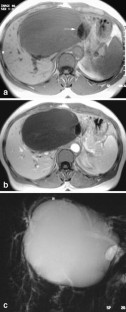

Magnetic resonance imaging (MRI) and magnetic resonance cholangio-pancreatography (MRCP) features were analyzed in the diagnosis of seven surgically resected hepatobiliary cystic tumors with reference to histopathological data. Homogeneity, size, location, signal intensity, presence or absence of septa and/or nodules and MRCP features of the lesions were studied. Histological evidence demonstrated six biliary cystadenoma (BCA) including four pseudo-ovarian stroma (POS) and one biliary cystadenocarcinoma (BCAC). Cystic lesions (3–15 cm in diameter) were homogeneous in the six BCA, heterogeneous in the one BCAC, and were located in the left and right liver, respectively. On T2-weighted images all lesions were hyperintense. On T1-weighted images hypointensity was found in three BCA (all serous fluid, including one POS), isointensity was found in the three others (two mucinous and one hemorrhagic fluid, including three POS) and in the one BCAC (containing mucinous fluid). Septas were present in all cases and nodules only in the one BCAC. On MRCP a hyperintense cystic lesion was found in all cases and a bile ducts dilatation in two BCA and the one BCAC. Gadolinium-enhanced MRI in combination with MRCP is a valuable tool for the diagnosis of BCA or BCAC. However, no specific information is gained for POS detection.

Fig. 1